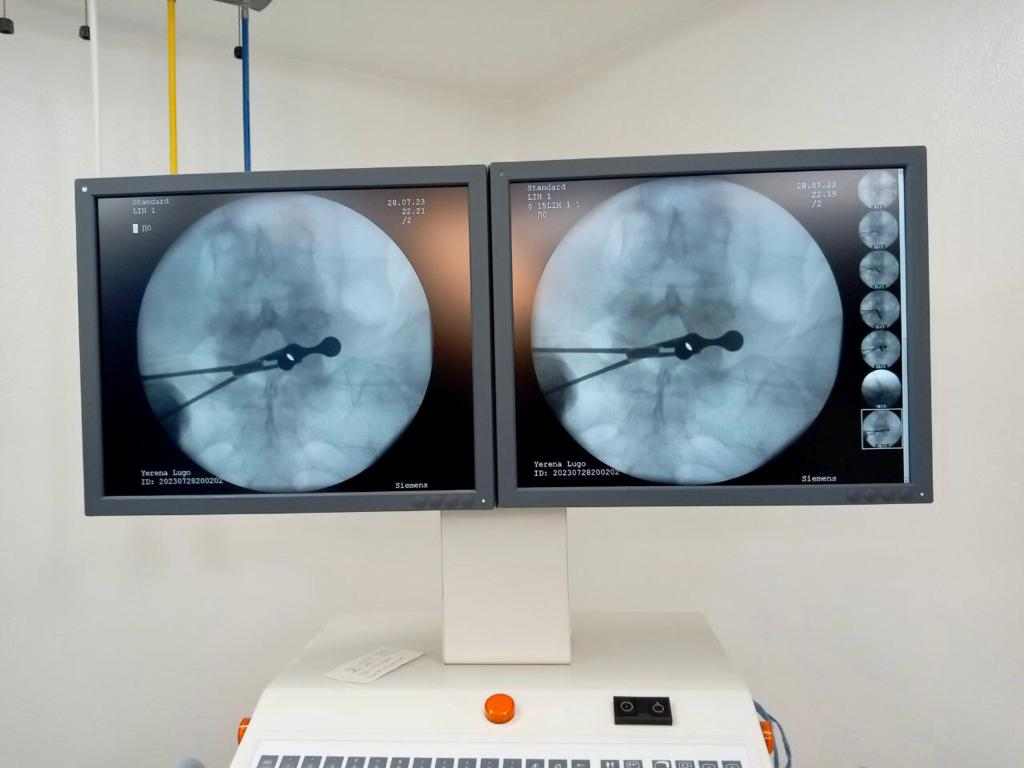

Esta cirugía es definida como “una técnica quirúrgica centrada en la exploración del canal espinal, mediante una cámara que cuenta con un sistema óptico como fuente de luz, conectada a su vez a una pantalla de alta definición” por tanto, consiste en la extirpación de la hernia discal “viendo” mediante una cámara y utilizando cánulas especiales, con la mínima invasión y daño posible, pero de forma más segura y con una recuperación mucho más rápida y confortable.

La explicación de este procedimiento detalla que para realizar esta cirugía revolucionaria, se anestesia al paciente y se le coloca en posición decúbito prono con almohadillas en el tórax y en la región pélvica; realizan una incisión de apenas 2 centímetros en la piel, colocan una cánula, en cuyo interior se introduce la óptica que permite ampliar el campo de trabajo; y una vez dentro del canal espinal, se realiza la separación de la raíz comprimida para extraer el fragmento herniado.